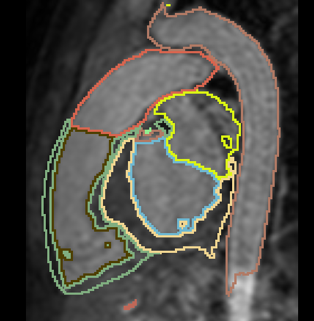

Interactive Deep Learning for Congenital Heart Disease Segmentation

- Aim: segment all cardiac chambers and great vessels from cardiac MRI, for children with congenital heart disease.

- 20 training cases + large anatomical variability - remains a challenge for automatic segmentation.

- Approach: Integrate some interaction from the user, e.g. scribbles or landmarks.